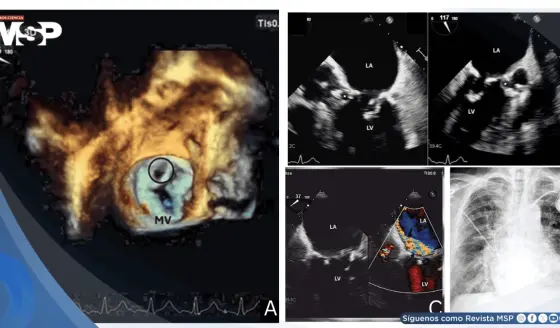

Endocarditis de Staphylococcus epidermidis tras implante de marcapasos causa pseudoaneurisma mitroaórtico